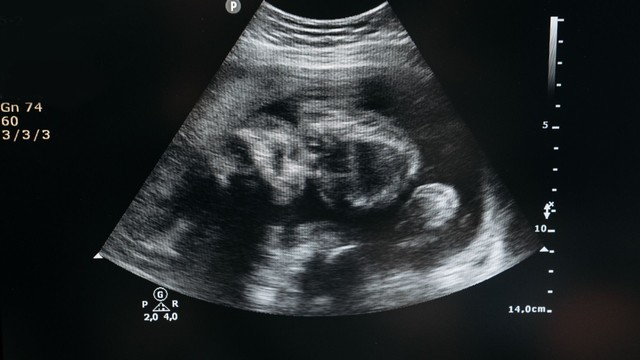

thai kỳ

Nhiều biến chứng thai kỳ nghiêm trọng có thể phòng được nhờ các mũi vắc xin phù hợp cho từng giai đoạn mang thai. Việc hiểu rõ mũi nào an toàn, mũi nào bắt buộc giúp mẹ bảo vệ cả mình lẫn em bé hiệu quả hơn.